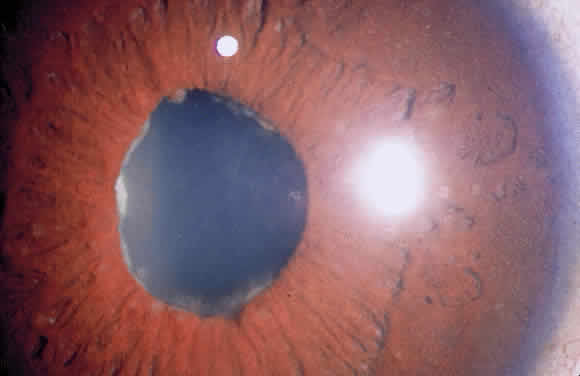

Cells in the anterior chamber are counted using the wide beam with a 1- to 2-mm long slit and graded according the method of Hogan and coworkers (Table 2).11 If the cells seem to be suspended rather than moving, there is probably extensive fibrin in the aqueous. Leukocytes may precipitate out of the anterior chamber to form a hypopyon (Fig. 5), and erythrocytes may layer out in a hyphema. It is important to examine the area of the inferior limbus, so that the presence of layered cells is not overlooked.